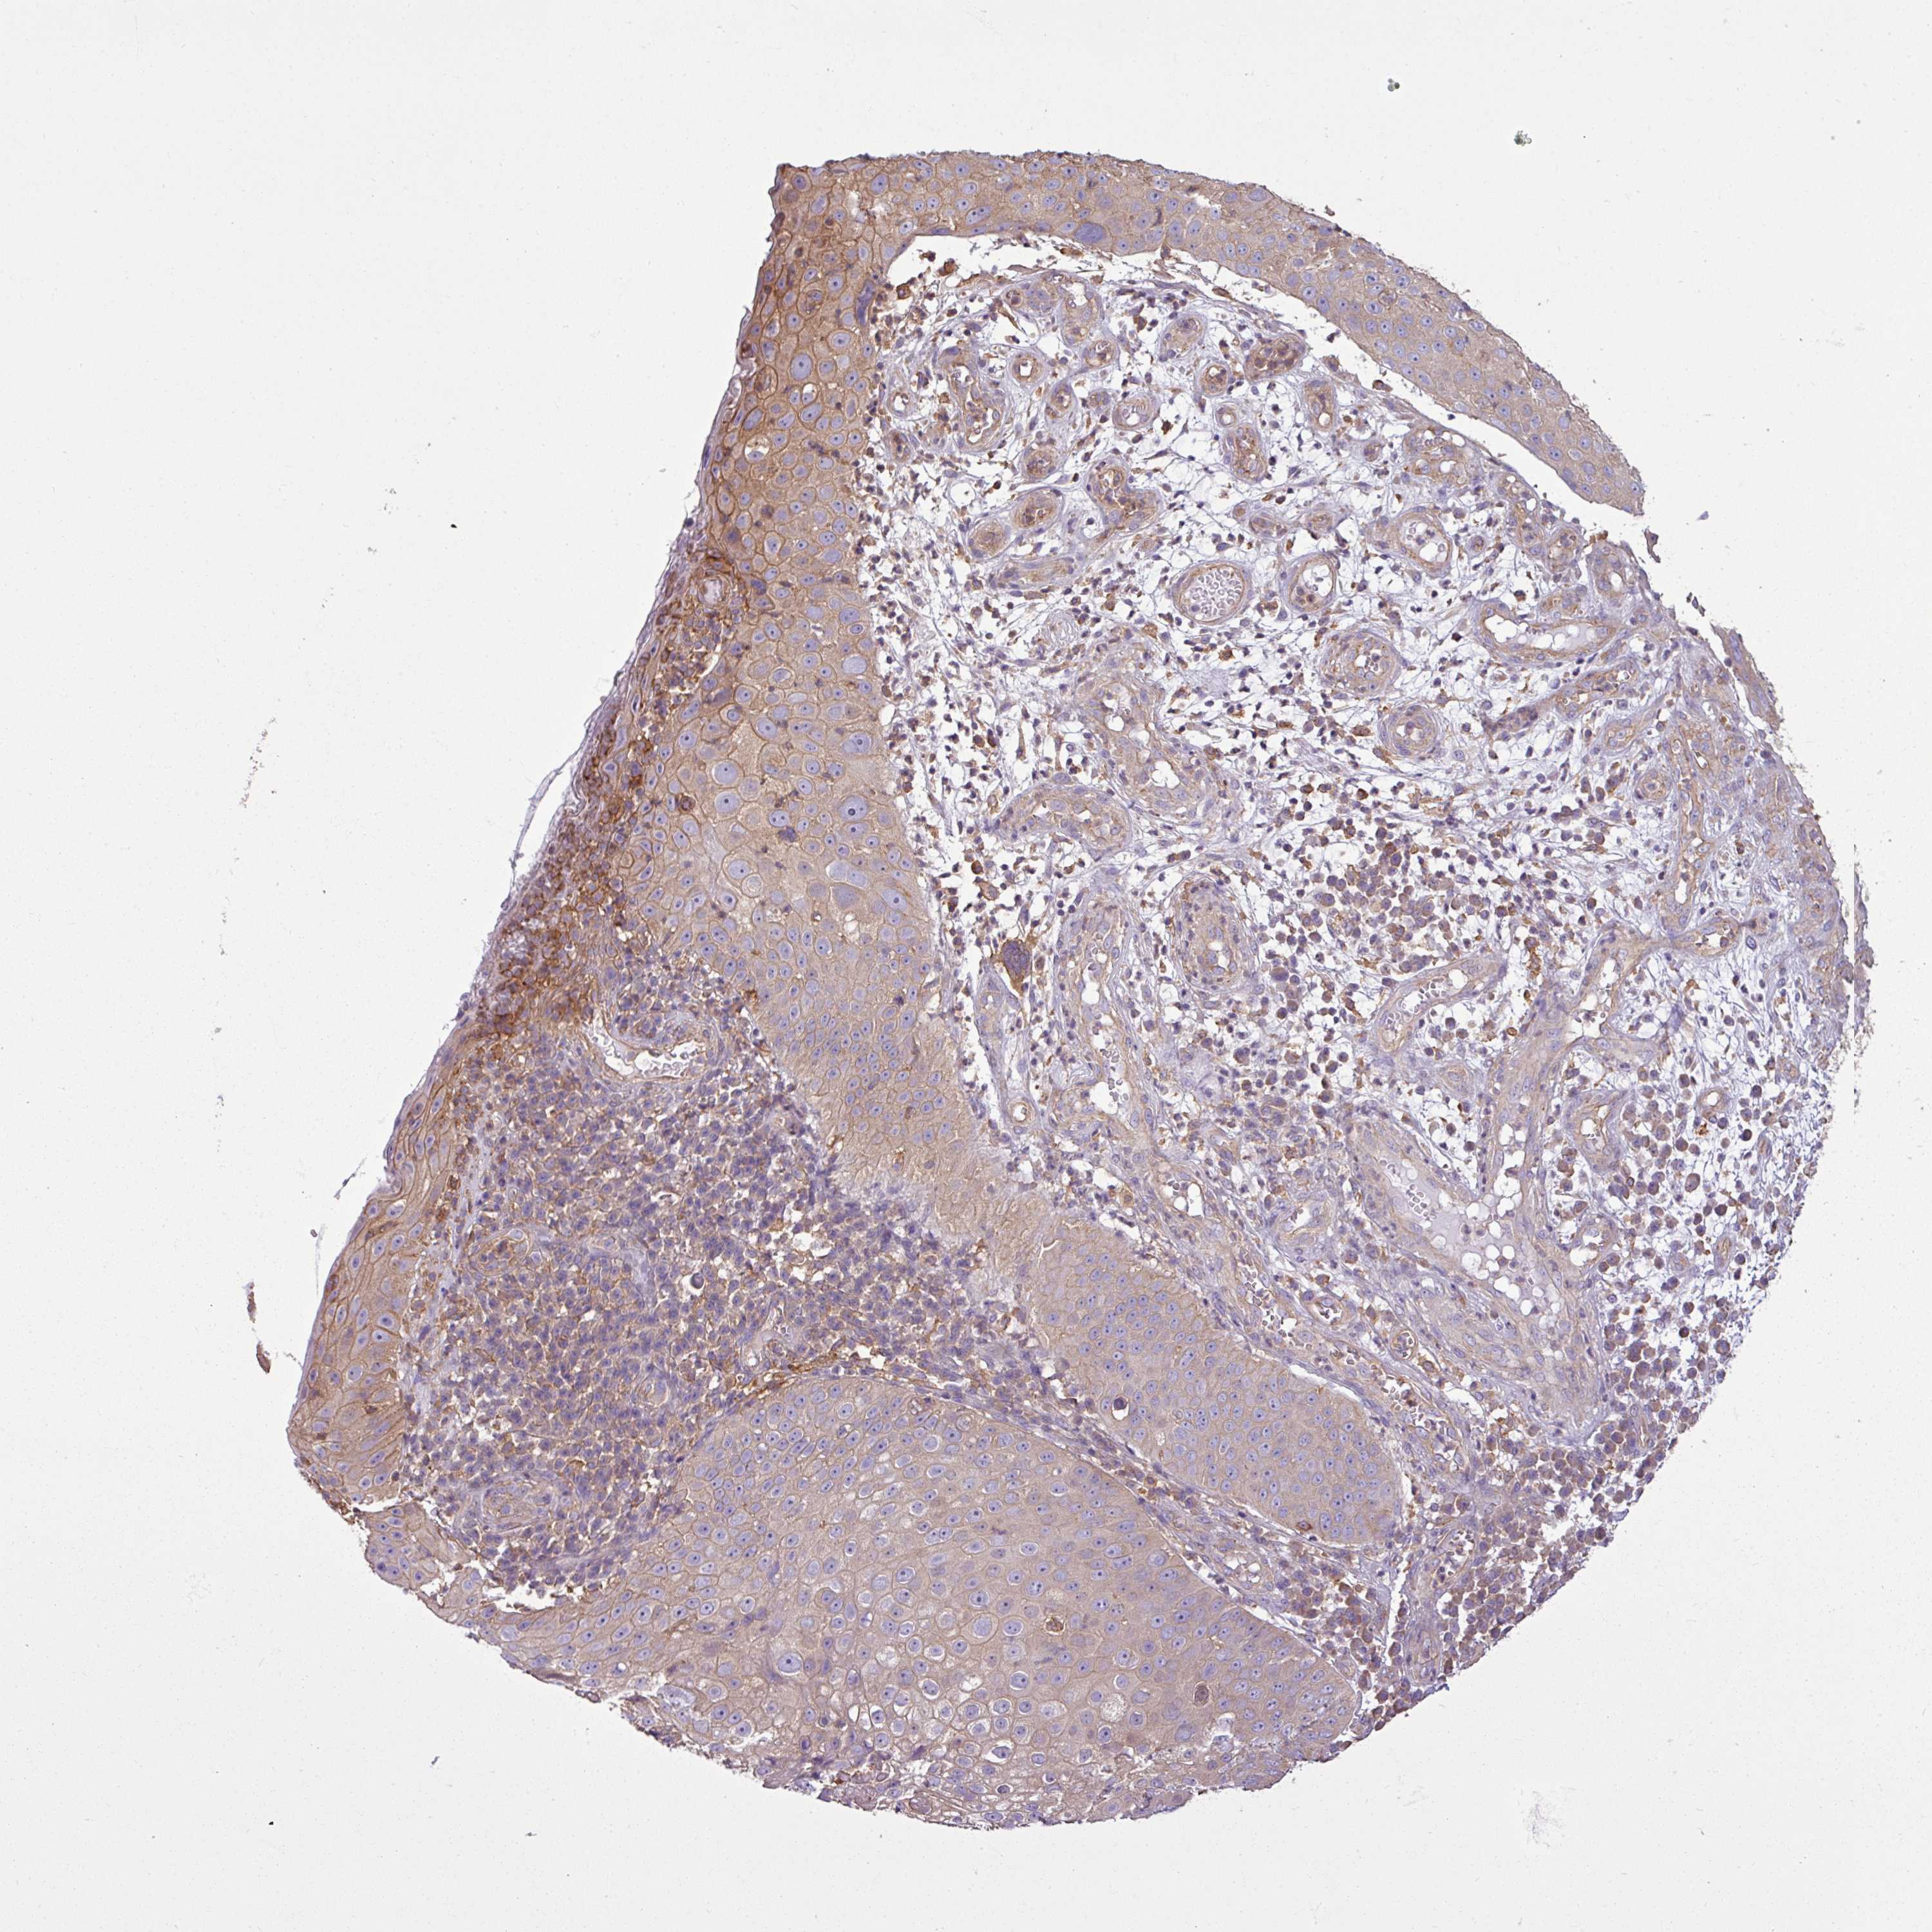

Basal cell and squamous cell cancer

SKIN CANCER - Protein expressioni

A mouse-over function shows sample information and annotation data. Click on an image to view it in a full screen mode. Samples can be filtered based on level of antibody staining by selecting one or several of the following categories: high, medium, low and not detected. The assay and annotation is described here.

Antibody stainingi

Antibody staining in the annotated cell types in the current human tissue is reported as not detected, low, medium, or high, based on conventional immunohistochemistry profiling in selected tissues. This score is based on the combination of the staining intensity and fraction of stained cells.

Each image is clickable and will lead to virtual microscopy that enables deeper exploration of all samples and also displays staining intensity scores, fraction scores and subcellular localization as well as patient and tissue information for each sample.

Antibody HPA049854

Antibody HPA056520

Staining

High

Medium

Low

Not detected

Intensity

Strong

Moderate

Weak

Negative

Quantity

>75%

75%-25%

<25%

None

Location

Nuclear

Cytoplasmic/membranous

Cytoplasmic/membranous,nuclear

Basal cell carcinoma

Squamous cell carcinoma, NOS

Squamous cell carcinoma, metastatic, NOS